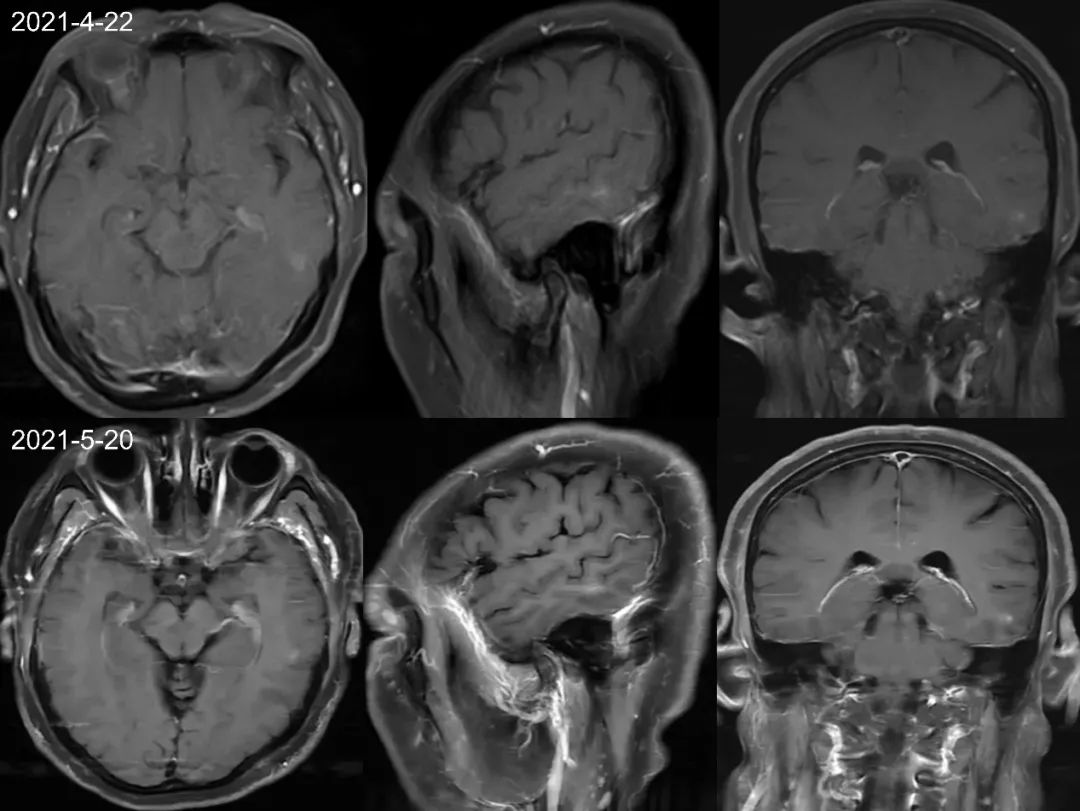

首次检查 2021-1-5 日发现左侧颞叶强化结节,轴矢冠状位都能看到,但是平扫看不到,周围亦未见水肿信号,此时没经验的诊断医生估计会考虑为转移瘤,一直困扰着患者和临床医生。但是在其余 7 次检查中 2021-3-2 至 2022-6-22 一年半多的时间,左侧颞叶强化结节仍然存在,并且基本没啥变化,如果是转移瘤会这么长时间无任何干预都处于一个静止状态吗?,此时是不是需要考虑其他的诊断?,究竟是什么呢,有经验的医生肯定会想到:是毛细血管扩张症。

仔细观察本例左侧颞叶强化结节,中心为明显强化,周围为稍淡淡样的强化,此为毛细血管扩张症的特点。